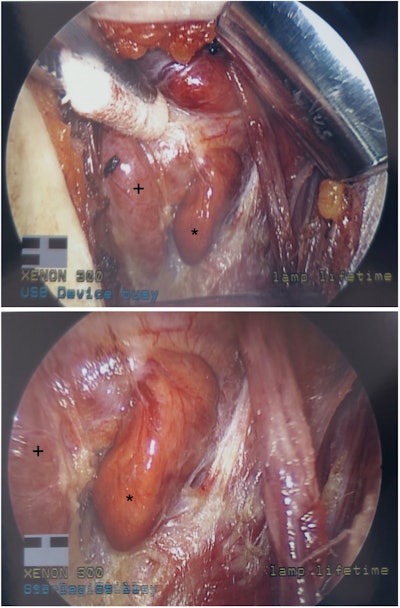

Once a diagnosis of primary hyperparathyroidism has been made and the physician and patient have agreed that surgery is indicated, imaging studies are useful for preoperative localization.1 Ultrasound is an excellent initial localization study. It is low cost, results in no radiation exposure for the patient, and is the best study for identification of coexisting thyroid pathology that may be present in up to 50% of patients. Ultrasonography is able to identify the abnormal parathyroid gland in 80%-90% of patients with single gland disease (Figure 1).

Figure 1. Intrathyroid left inferior parathyroid adenoma with polar blood flow pattern.Figure 1. Intrathyroid left inferior parathyroid adenoma with polar blood flow pattern.